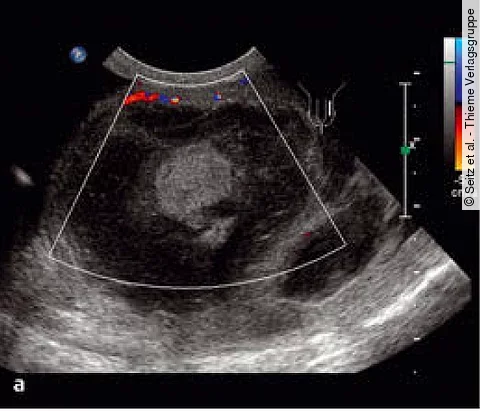

Uro-QuizVergrößerter Hoden: Nur ein Hämatom?

Ein 47-jähriger Mann mit Schwellung des linken Skrotalfachs, Schmerzen und Traumaanamnese stellt sich vor.